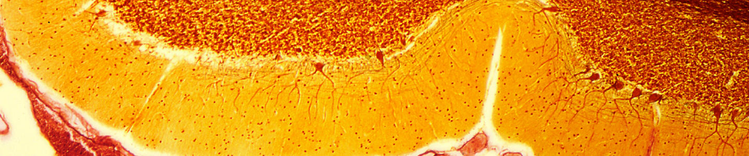

CÉLULAS DE PURKINJE NO CEREBELO